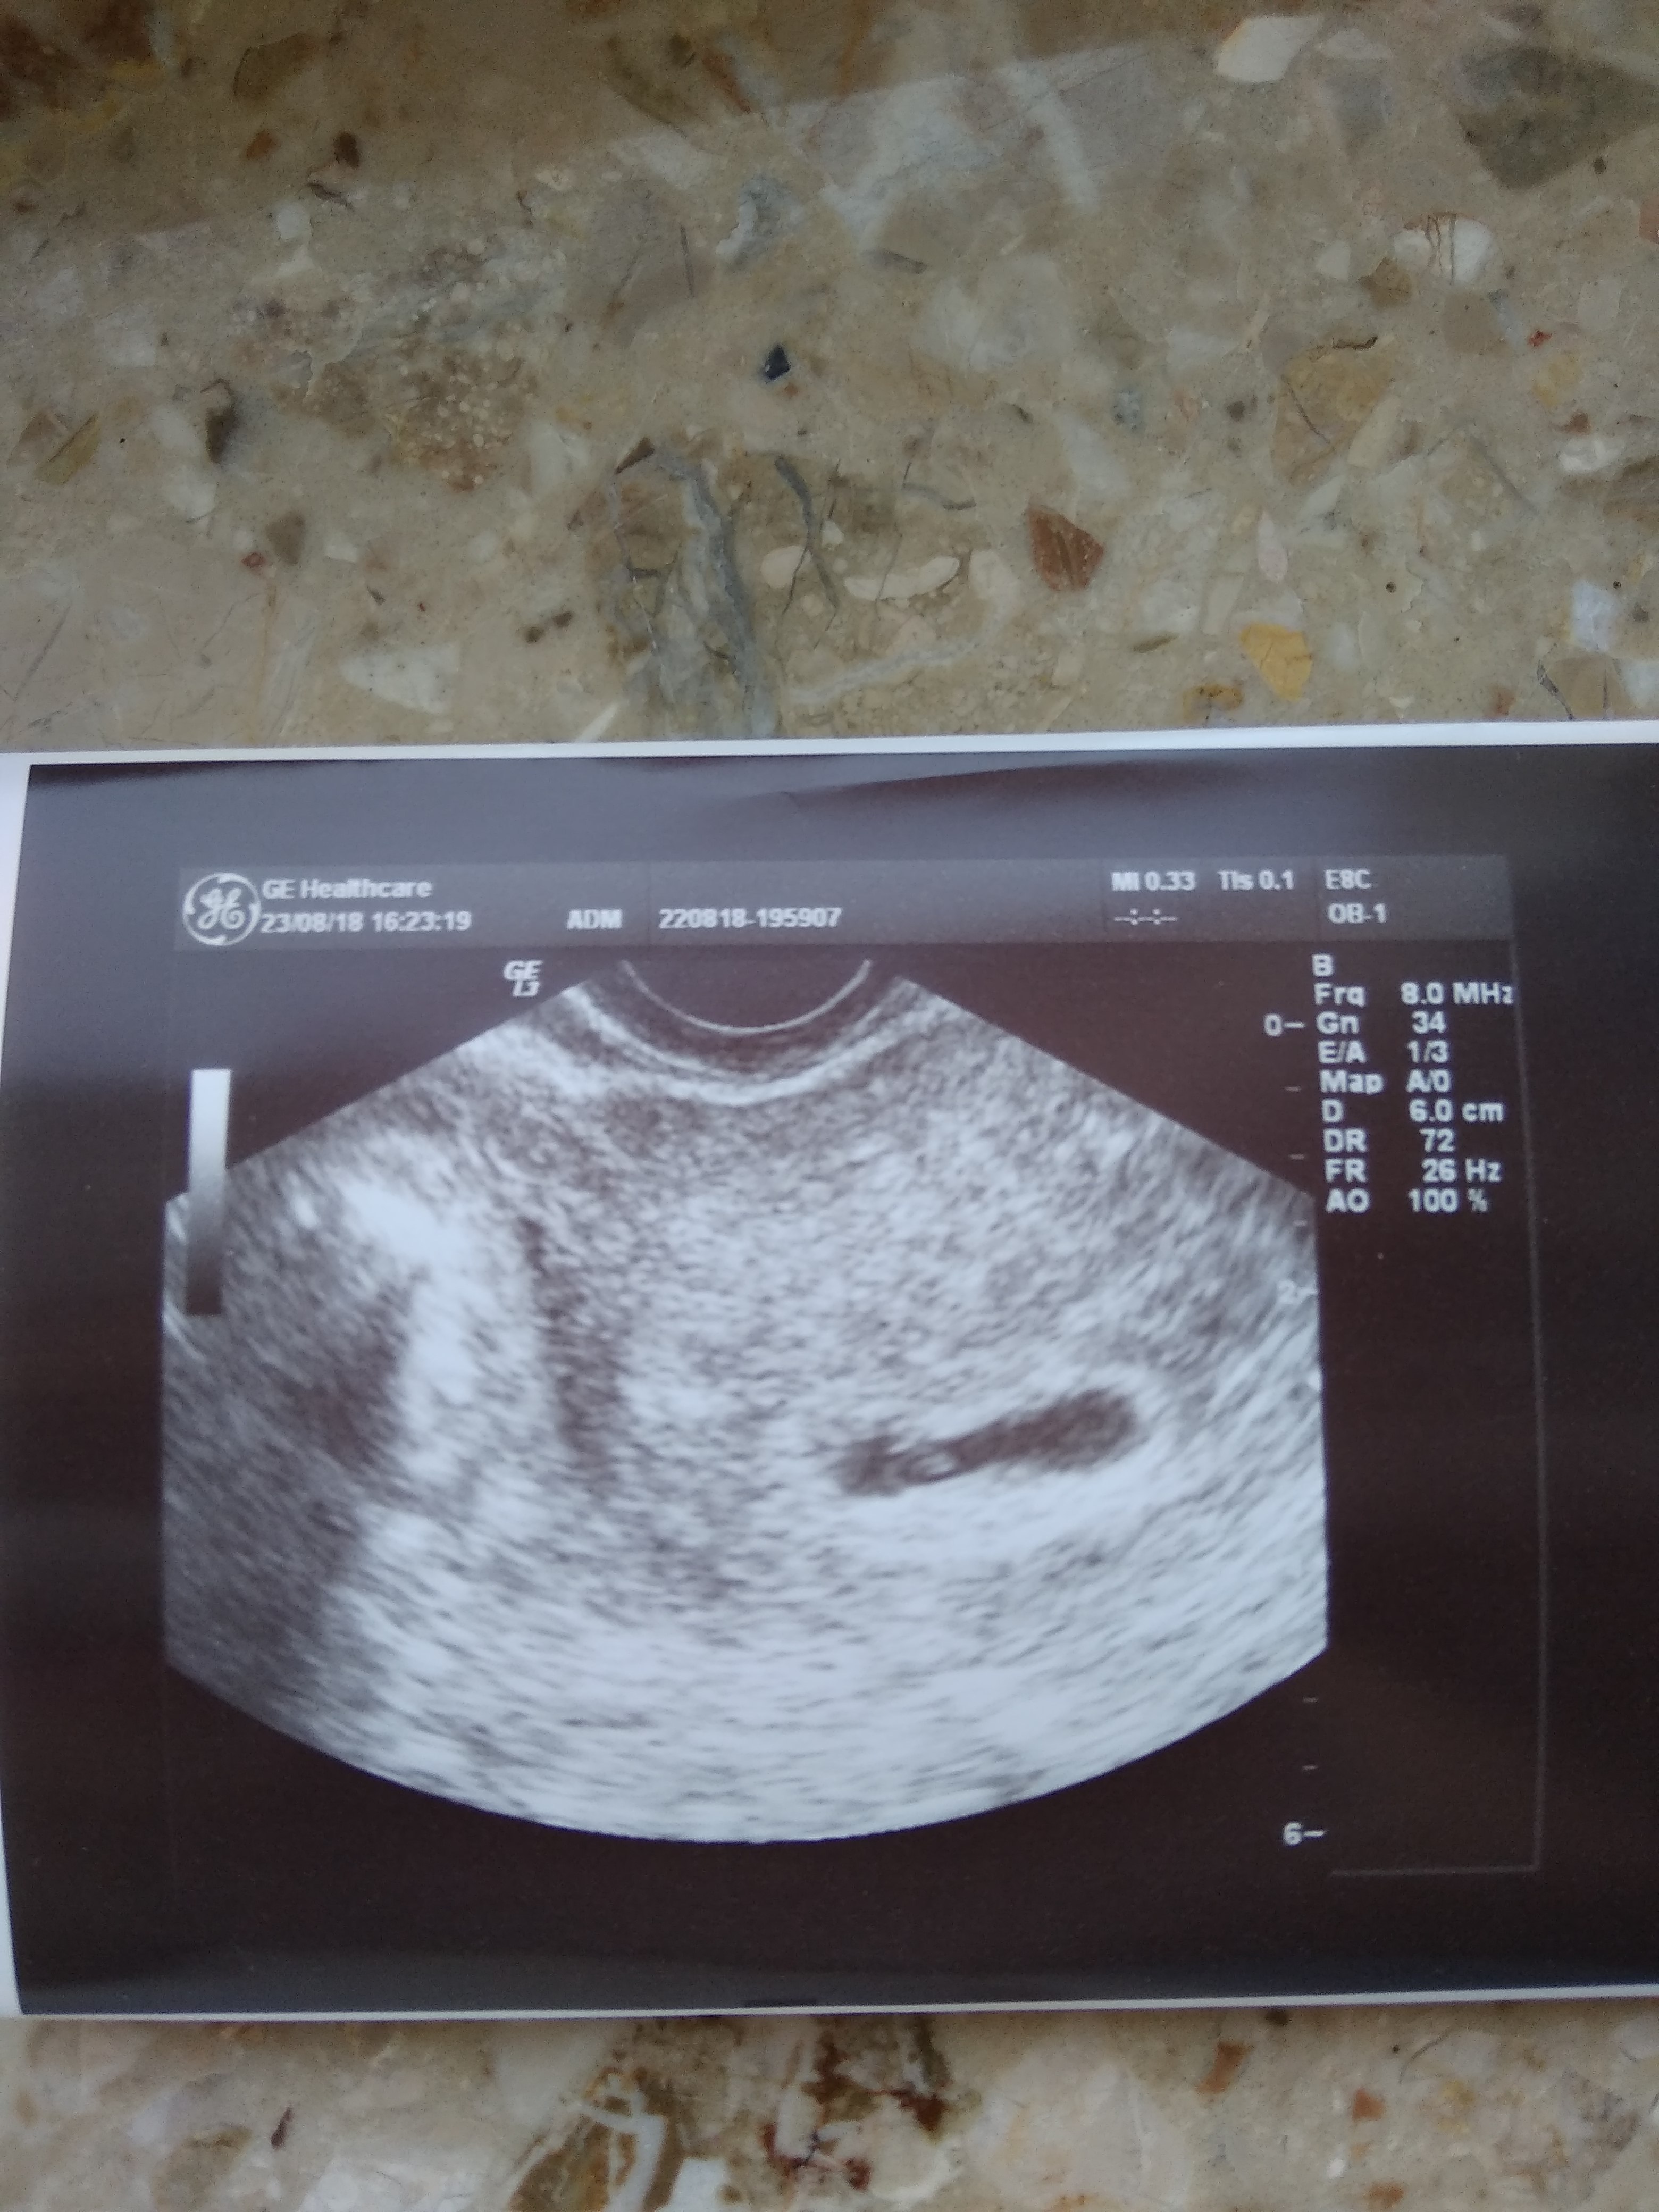

Byłam dziś na wizycie 5 tyg i 3 dni jest pęcherzyk i echo zarodka wszystko na miejscu dołączam zdjęcie kropka.Kolejna wizyta 10 września mam porobić badania i założy mi kartę ciąży

Załączniki

• IMG_20180823_180946.jpg